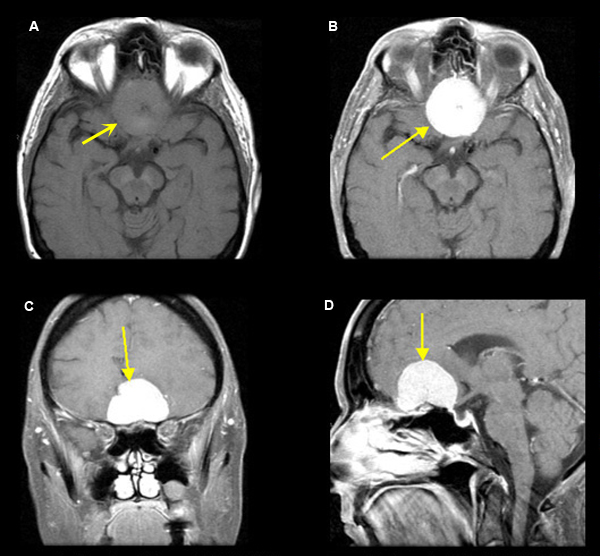

Figure 1

A. Pre-contrast axial T1 wtd. MRI

B. Post-contrast axial T1 wtd. MRI

C. Post-contrast coronal T1 wtd. MRI

D. Post-contrast sagittal T1 wtd. MRI

Case 1:

80 year old patient presents with anosmia and short term memory loss.

Imaging findings: Figure 1

• A well defined strikingly enhancing classic meningioma is seen involving the floor of anterior cranial fossa (yellow arrow in figs B, C, D).

• The tumor is dural based and is extra-axial.

Final impression:

Meningioma